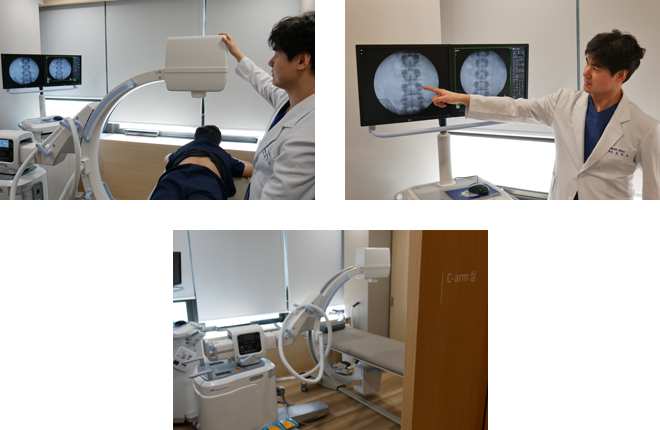

대치역삼바른길정형외과의 신경차단술 차별점

대치역삼바른길정형외과의원에서는 안전하고 정확한 시술을 위해

정확도가 뛰어난 정밀진단 장비를 사용하고 있습니다.

뼈와 관절을 실시간으로 볼 수 있는 디지털, 포터블 엑스레이 장비입니다.

이를 바탕으로 정밀한 진단과 안전한 시술이 가능합니다.